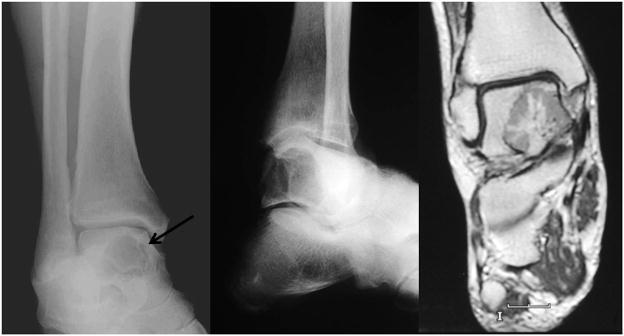

The patient was a 67-year-old man with a 7 month history of increasing pain in the right foot and ankle. Initial radiographic studies revealed a 2 cm lytic lesion of the right talus with focal overlying cortical erosion (Fig. 1). No extension into the soft tissue was identified. Subsequent physical examination and imaging studies failed to demonstrate evidence of other osseous or non-osseous lesions.

Figure 1.

A. Preoperative anteroposterior mortise and B. Broden’s view radiographs of the affected ankle showing a well-defined lytic lesion involving the body of the talus (arrow). No matrix calcification is identified. C. Coronal T1-weighted image after administration of gadolinium based contrast. Talus lesion demonstrates differential enhancement, most marked centrally with radial pattern. Several small foci of non-enhancement also present within lesion and persisted on other pulse sequences.